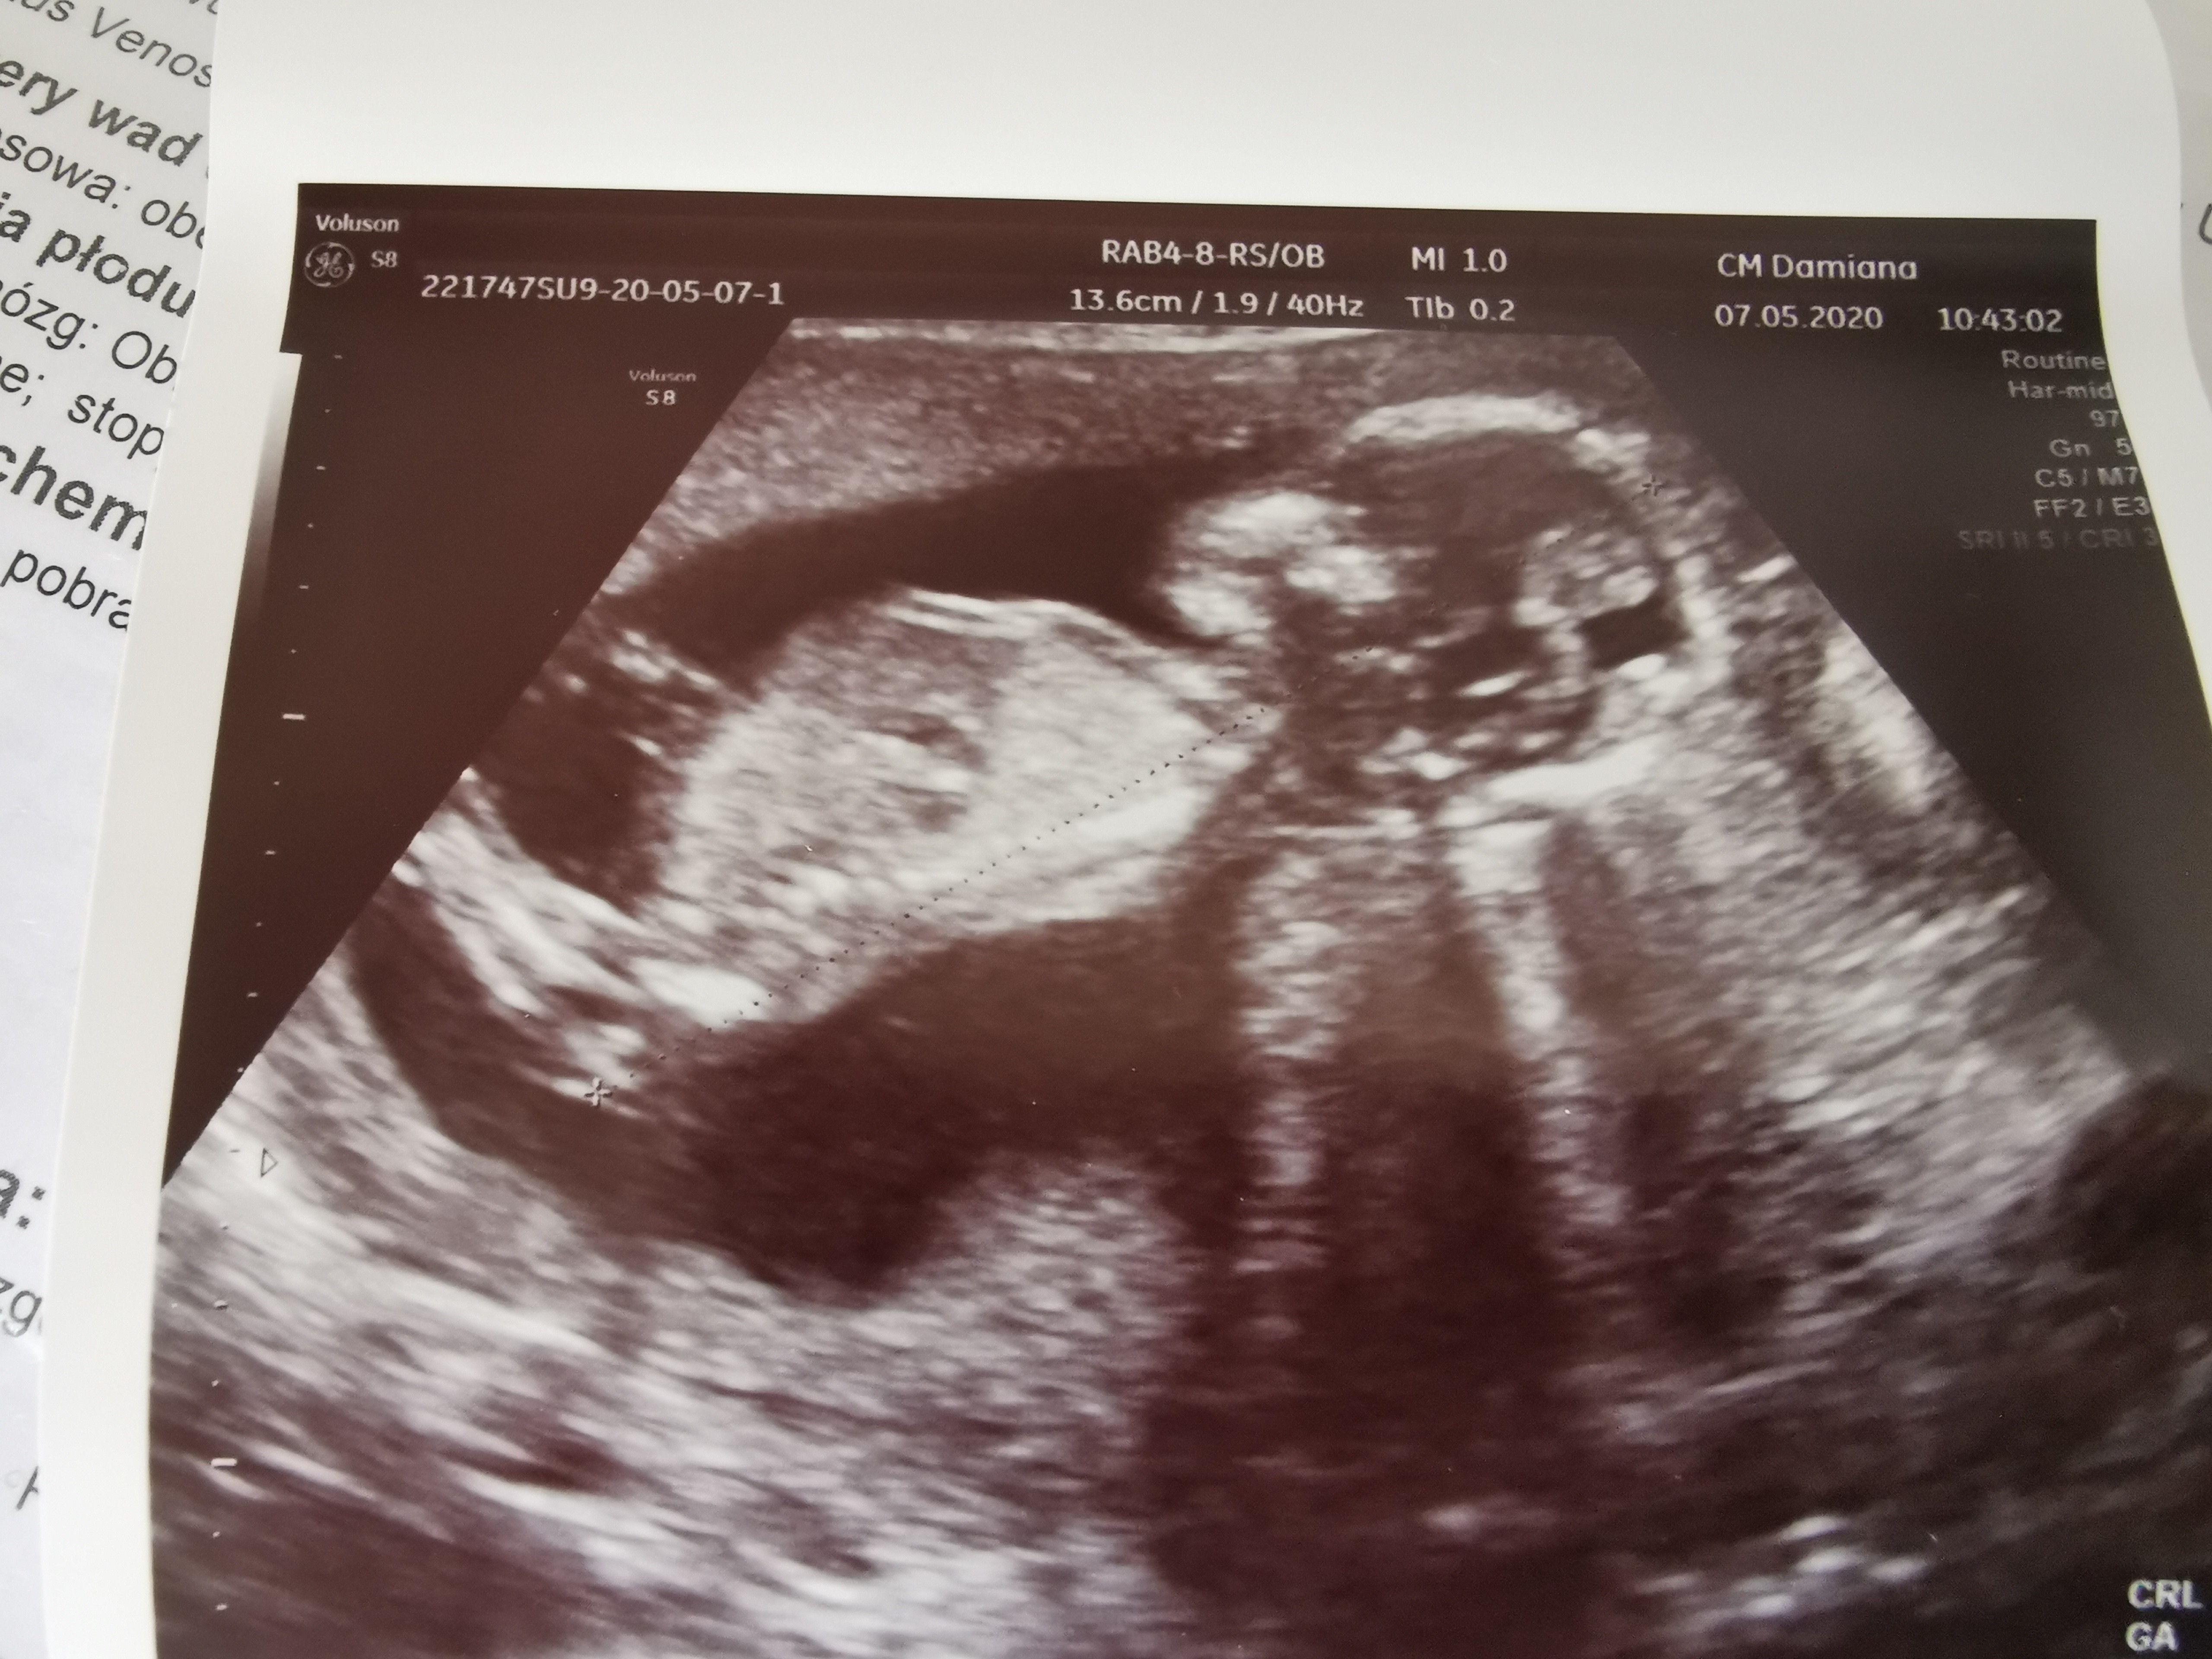

Tak, już doczytałam rozmiary i macie racjęBędzie w sobotę, do poniedziałku już ta druga mogła by być też przejrzała.. Tym razem się z nim zgadzam jak pokazał mi wymiary i porownalam z wynikami badań